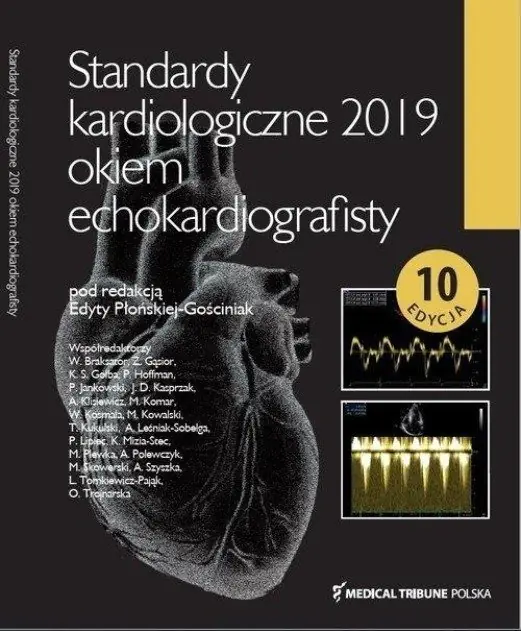

Standardy kardiologiczne 2019 okiem echokardiografisty

Opis książki przedstawia najnowsze wytyczne związane z różnymi aspektami kardiologii. Pierwsza część koncentruje się na opiece nad kobietami w ciąży, które zmagają się z chorobami serca. Nowe klasyfikacje dotyczą oceny ryzyka sercowego, a także uwzględniają wady zastawkowe zarówno nabyte, jak i wrodzone, nadciśnienie tętnicze i płucne, kardiomiopatie oraz chorobę wieńcową.

Dalsza część książki opisuje procesy rewaskularyzacyjne w kontekście stabilnej choroby wieńcowej oraz w przypadkach STEMI i nSTEMI. Książka przedstawia również zaktualizowaną definicję zawału serca. Aby ułatwić przyswojenie zaleceń, zastosowano wizualizacje diagnostyczne i postępowanie przy użyciu echokardiografii.

Osobny rozdział poświęcono elektrokardioterapii, szczegółowo omawiając działania niepożądane oraz procedury usuwania elektrod. Ponadto, książka porusza zasady kompleksowego obrazowania dorosłych pacjentów z wrodzonymi wadami serca, co stanowi istotny element całościowego podejścia do diagnostyki.

Opis książki przedstawia najnowsze wytyczne związane z różnymi aspektami kardiologii. Pierwsza część koncentruje się na opiece nad kobietami w ciąży, które zmagają się z chorobami serca. Nowe klasyfikacje dotyczą oceny ryzyka sercowego, a także uwzględniają wady zastawkowe zarówno nabyte, jak i wrodzone, nadciśnienie tętnicze i płucne, kardiomiopatie oraz chorobę wieńcową.

Dalsza część książki opisuje procesy rewaskularyzacyjne w kontekście stabilnej choroby wieńcowej oraz w przypadkach STEMI i nSTEMI. Książka przedstawia również zaktualizowaną definicję zawału serca. Aby ułatwić przyswojenie zaleceń, zastosowano wizualizacje diagnostyczne i postępowanie przy użyciu echokardiografii.

Osobny rozdział poświęcono elektrokardioterapii, szczegółowo omawiając działania niepożądane oraz procedury usuwania elektrod. Ponadto, książka porusza zasady kompleksowego obrazowania dorosłych pacjentów z wrodzonymi wadami serca, co stanowi istotny element całościowego podejścia do diagnostyki.

Okładka: Miękka

Ilość stron: 184

Rok wydania: 2019

Rozmiar: 210 x 277 mm

Autorzy: Edyta Płońska-Gościniak, W opisie

Wydawnictwo: Medical Tribune, Medical Tribune, W opisie